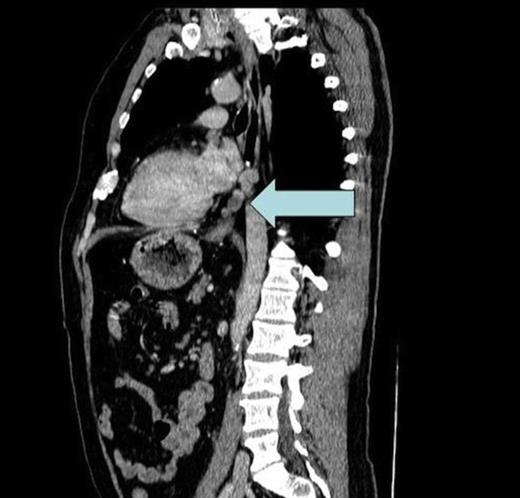

CT scan showing enlarged soft tissue deposits in a left paraoesophageal, pre-aortic site within the posterior inferior mediastinum

Suspecting occult pancreatic pathology a computerised tomography (CT) of the chest, abdomen and pelvis was performed. There was occult fibrosis post splenectomy and mild anatomical distortion at the tail of the pancreas and left diaphragm. However, the scan also identified enlarged soft tissue deposits in a left paraoesophageal, pre-aortic site within the posterior, inferior mediastinum (level of D8-D10); the largest deposit measuring 18mm in diameter (Fig. 1). Structures normally residing here are predominantly lymph nodes and at this size would suggest pathological enlargement.